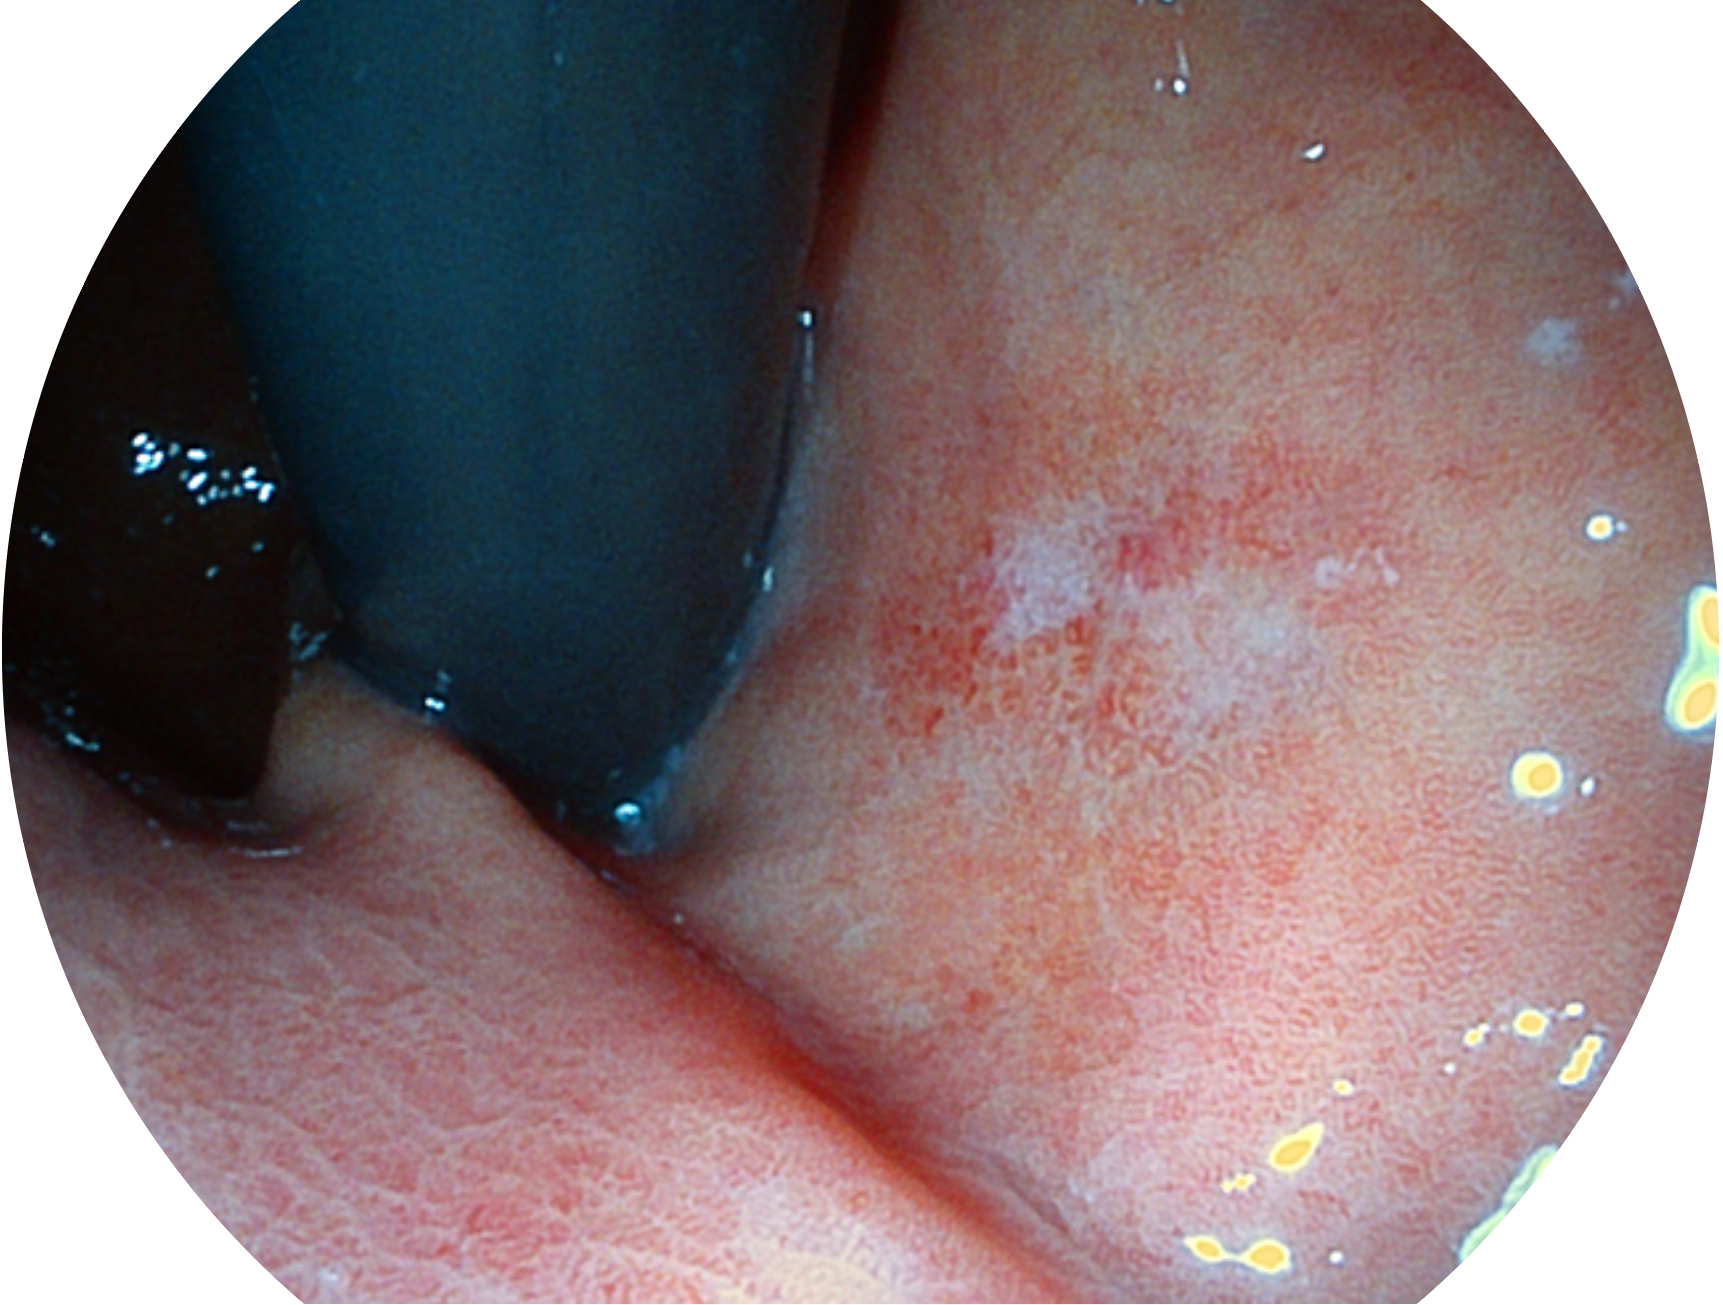

與上一代VIST相比,摒棄了濾光轉(zhuǎn)輪而直接采用光譜組合的方案,加入了血紅蛋白吸收高峰與次高峰的藍(lán)紫光和綠光光譜,更有利于黏膜血管吸收,突顯淺表層血管和中層血管的對比度,因而具備更高的圖像對比度,近景觀察時(shí),有助于微細(xì)結(jié)構(gòu)變化及病灶邊界的觀察。

• 白光圖像 VIST圖像